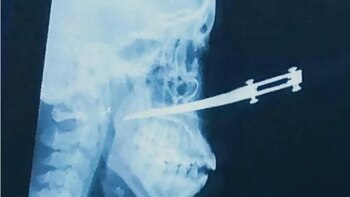

El nuevo caso se presentó en el barrio El Pózon, una mujer identificada como Yoleydis Montaban Hernández, de 35 años, quien se desempeña como guarda de seguridad de un centro comercial en la ciudad y se dirigía a su lugar de trabajo, fue interceptada por dos sujetos que la amenazaron con armas blancas, pero al mostrar un poco de resistencia, los hombres la agredieron varias veces con un cuchillo que al final terminó incrustado en su nariz.

Ambos llegaron al Centro de Atención Permanente de El Pozón, ubicado a dos cuadras de donde ocurrieron los hechos, allí fue atendida por el personal de salud y posteriormente fue remitida a la Clínica La Ermita en donde le fue practicada una cirugía maxilofacial, ya que también presentaba otra herida en el cachete del mismo lado donde le incrustaron el arma corto punzante.

“Por la nariz le entró el cuchillo, eso era muy delgadito, afortunadamente no le llegó a la columna, el cuchillo le llegó hasta un poquito más allá de la garganta, pero por fortuna no le dañó ningún órgano. Me siento impotente, sentí ganas de correr tras ellos para que me mataran, pero era más importante atender a mi hija”, argumentó Humberto.

La joven fue intervenida quirúrgicamente y en los próximos días se definirá si es necesario que sea sometida a una reconstrucción de rostro por parte de un cirujano plástico.